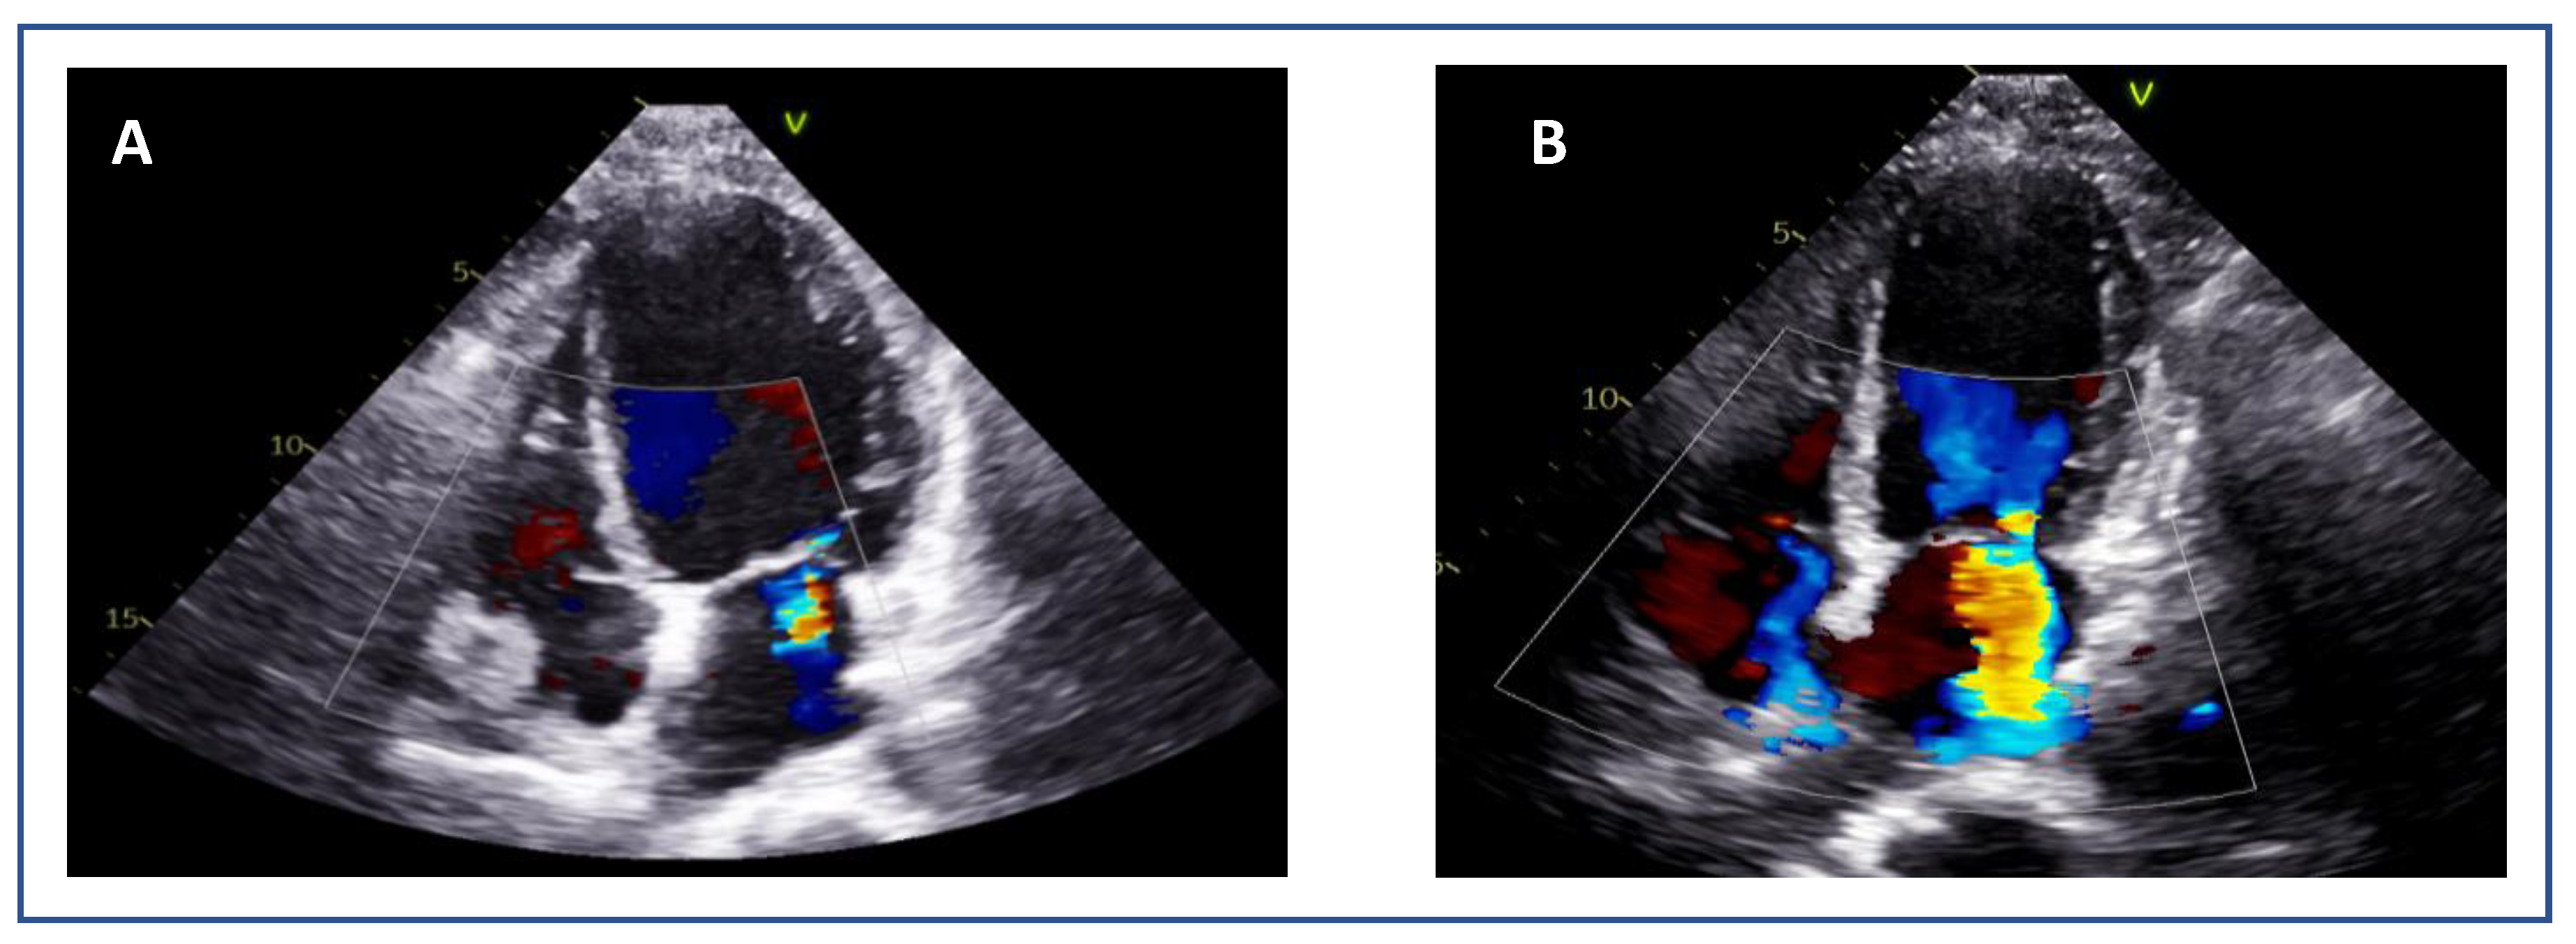

7.5. Tenting Height and Coaptation Length (SMR)

Adequate but Tethered LeafletsPosterior leaflet length may be sufficient, but severe tethering reduces coaptation and grasping success (Figure 11).